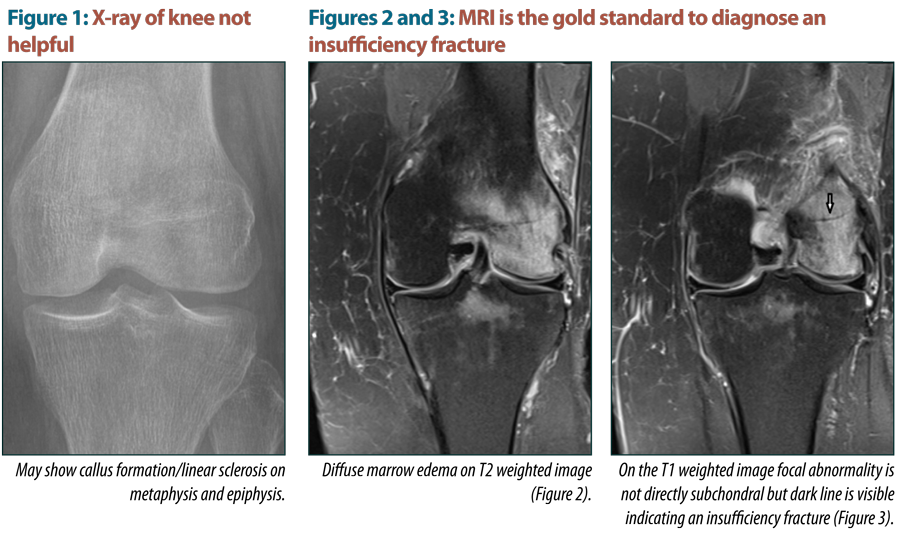

Abstract: Insufficiency Fractures (I.F) are non-traumatic fractures that occur in abnormal bone (low density bone). Usually occurs in elderly post-menopausal women and is non-traumatic. X-rays are unremarkable and MRI showed extensive bone marrow oedema and subchondral fracture.

MRI is the gold standard for Dx. I.F.

Symptoms and conventional tests may not be helpful, High Index of suspicious is needed.